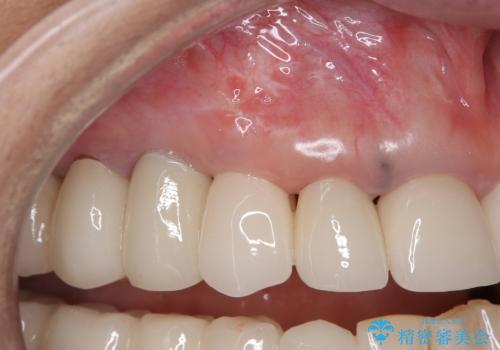

他の部位にインプラント治療を行っていたことから、こちらの歯に対してもインプラントによる補綴治療を希望されたため、1泊での帰国時に抜歯、インプラント埋入、仮歯の装着を行い、数ヶ月後の帰国時にオールセラミッククラウンの型取りと装着を行う計画としました。

インプラント埋入時は1泊、補綴治療時には3週間ほど日本に滞在していただき、2回の渡航で無事に治療を終えることができました。